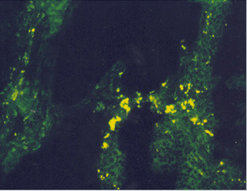

임상증상4

사진32 사진33 사진34

설명32 설명33 설명34